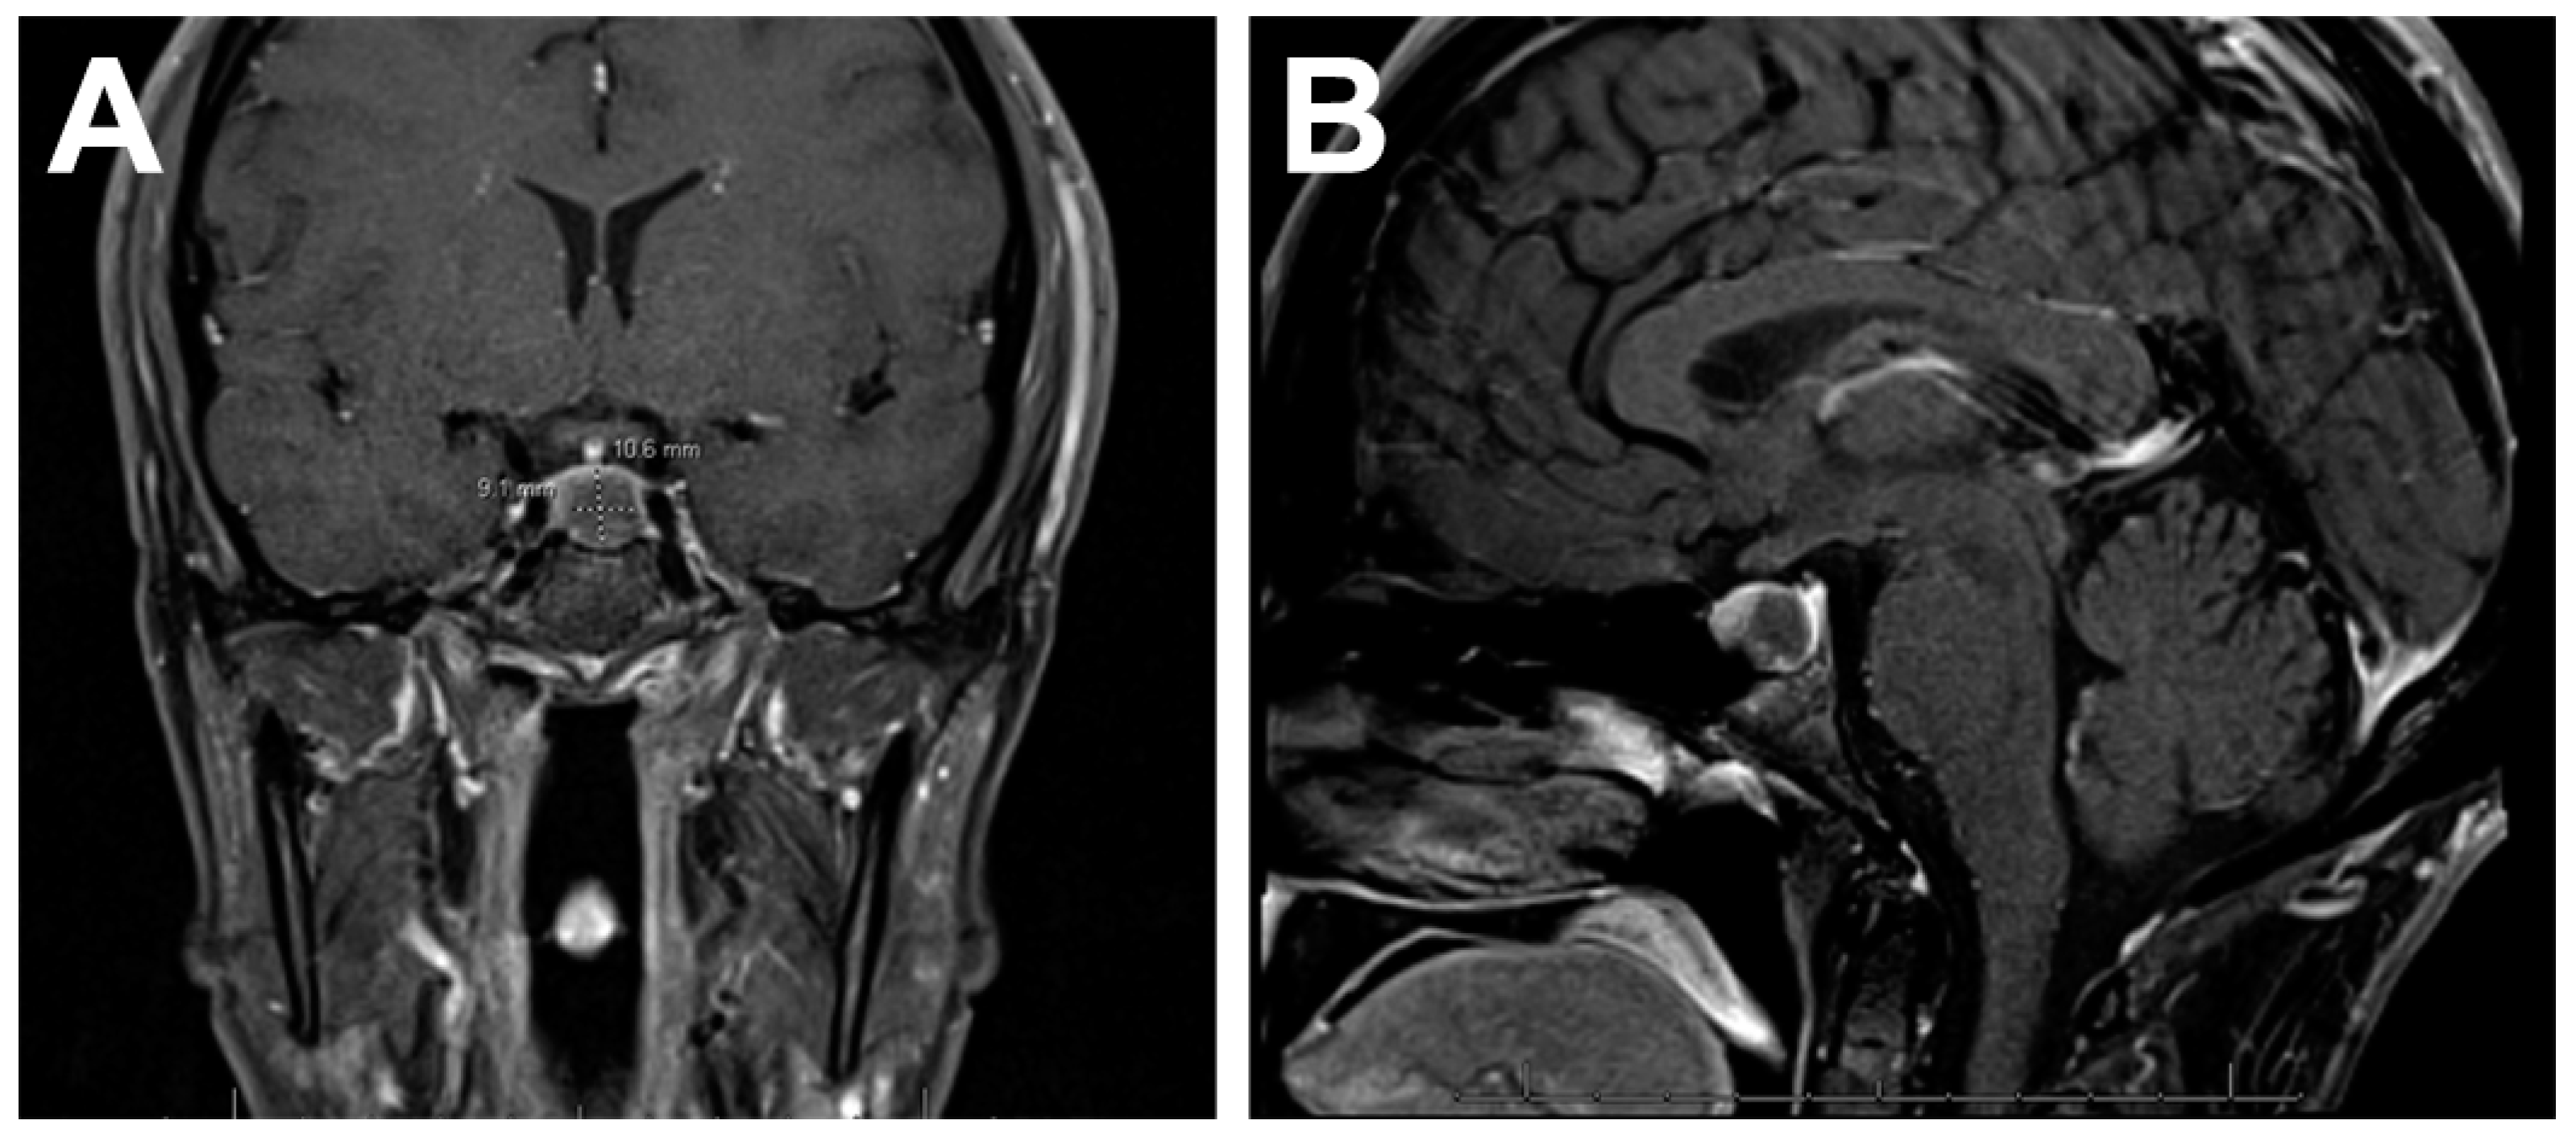

4.1. Imaging Features